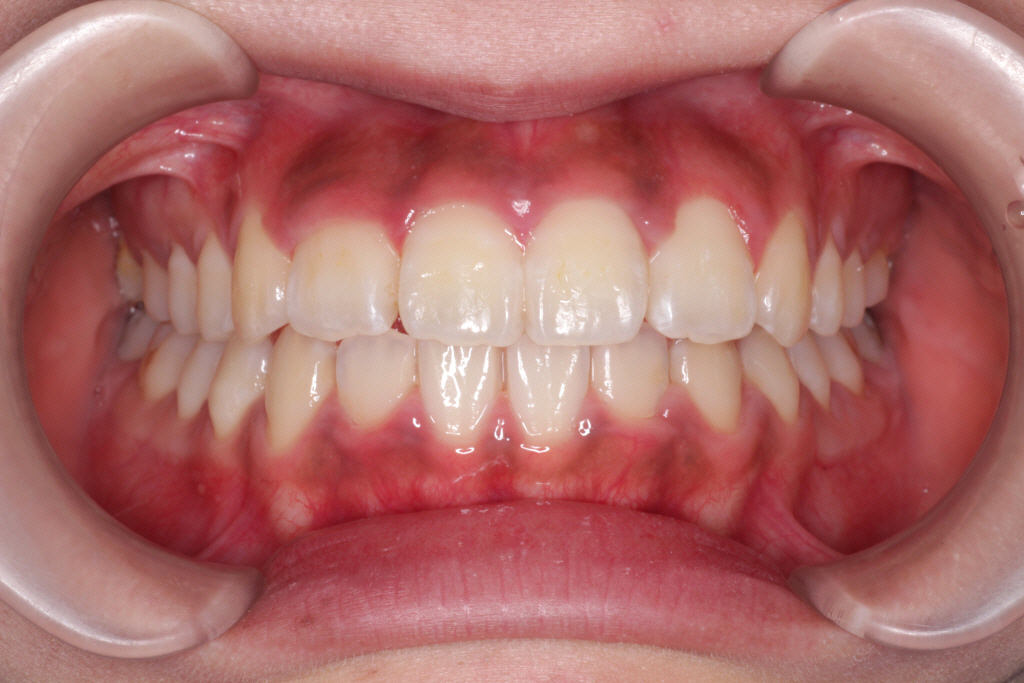

6ヶ月後、今回はだいぶ並んできました。↓

●改善点の結果

① 左上の2番目の歯は歯列に入りましたが、まだ少しねじれています。

② 右上の2番目の歯の切端咬合が、下の歯より上の歯が前方に出て、正常になりました。

③ 側方の噛み合わせが上1本に対して、下2本になりました。きれいに改善されました。

④ 噛み合わせがよくなり隙間がなくなりました。こちらも改善されました。

②~④の症状は解決したので、あとは①を改善するようにリファイメント3回目を行います。